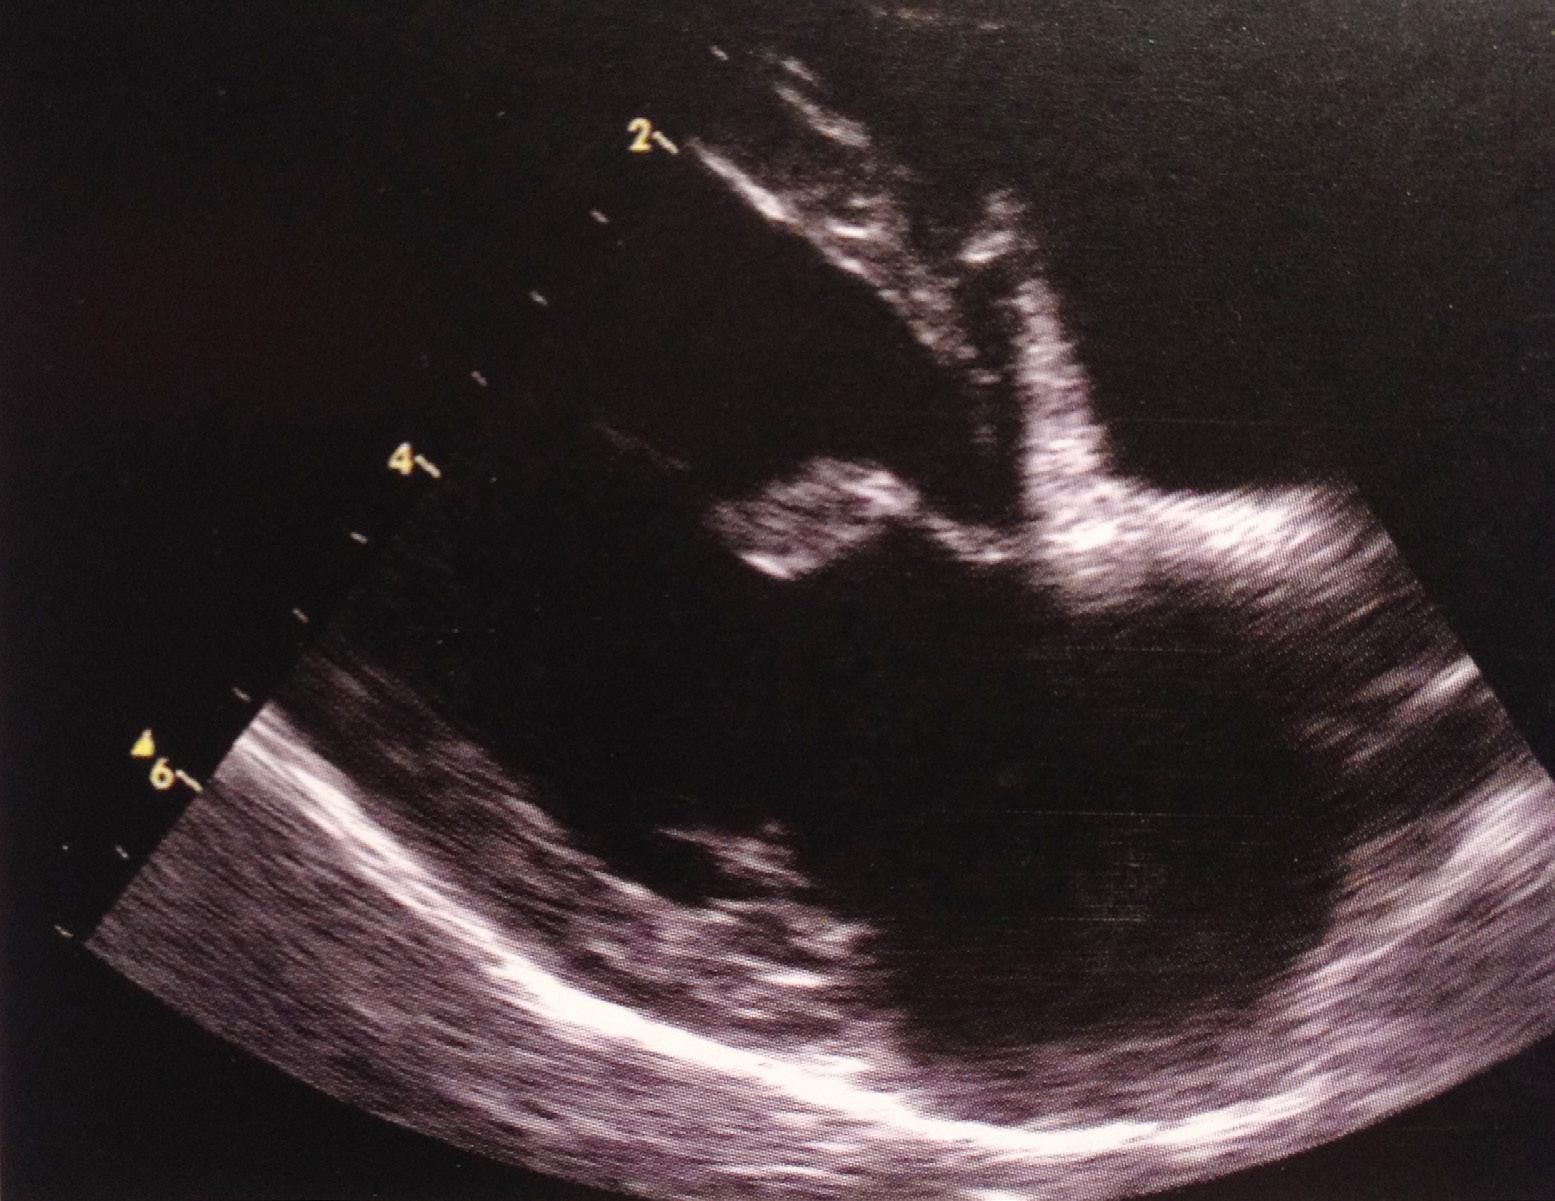

En grundig klinisk undersøgelse er vigtig i vurderingen af hjertesygdom. Lytning med stetoskop gør det muligt at vurdere mislyden og kan i mindre omfang afsløre væske i lungerne i de mere fremskredne tilfælde. I de fleste tilfælde er fordelene ved elektrokar-

Ultralydsbillede af hjerte af normal størrelse og med tynd mitralklap.

diogram (EKG) begrænsede, da hjerterytmeforstyrrelser er sjældne ved denne tilstand, og forstørrelse af hjertet vurderes mere præcist ved ekkokardiografi (ultralyd). Ultralyd har revolutioneret diagnosticeringen af MVD og er det mest hensigtsmæssige i de fleste tilfælde. Dette er en ikke-invasiv procedure, bedøvelse af hunden er normalt unødvendigt, og resultatet fås med det samme. Historisk er røntgenstråler blevet brugt til at vurdere forstørrelse af hjertet, men de kan kun bruges til vurdering af hjertets yderside. Røntgenstråler er dog stadig yderst nyttige til at vurdere lungefunktion og til at diagnosticere potentiel væske i lungerne. Det kan være nødvendigt at bedøve hunden, og ved hunde, hvis vejrtrækning allerede er påvirket, er en omhyggelig risikovurdering her yderst vigtig.

Ultralydsbillede af fremskreden MVD. Læg mærke til formen på mitralklappens flade og det forstørrede venstre forkammer.